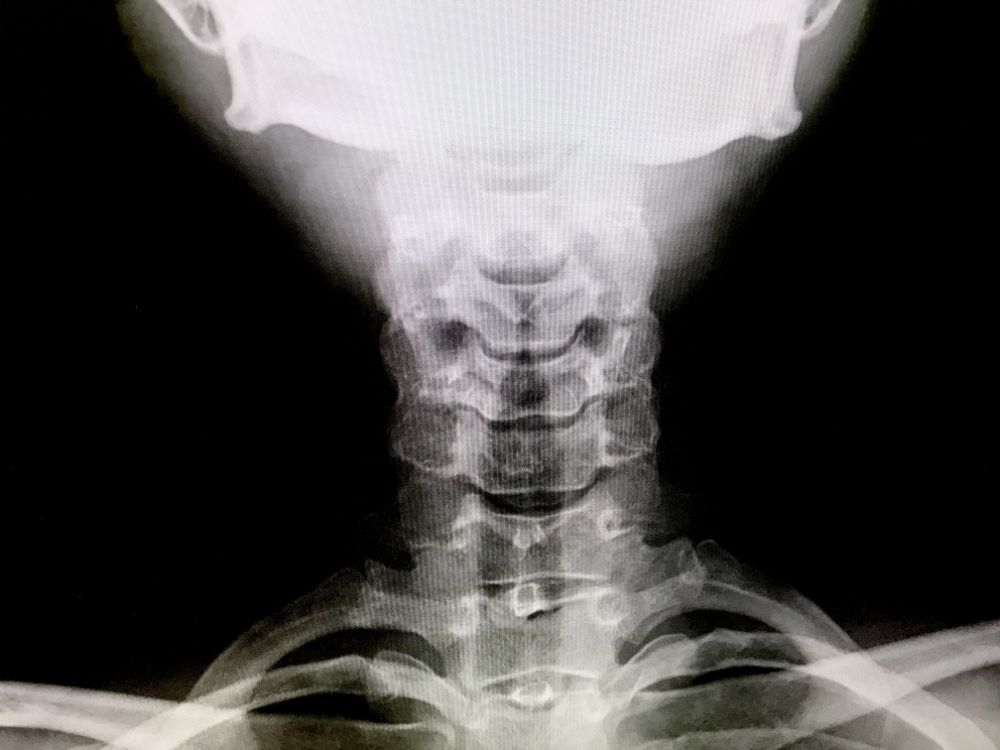

むちうちは、頚椎やその周囲の組織に衝撃が加わることで起こります。軽度のむちうちは頚椎捻挫と呼ばれており、自然に改善することも珍しくありません。

ただ、交通事故の衝撃が神経にまで及んだ場合、首や肩の痛みだけではなく、手のしびれや吐き気、めまい、耳鳴りといった症状が出ることもあります。むちうちがなかなか治らない原因として、検査をしても異常を発見しにくいことが挙げられます。

むちうちは発症に気づくのが遅れてしまうと、治療に要する時間も長くなってしまいます。そのため、事故の後は必ず病院で検査を受け、何らかの異常を感じたらすぐに治療を開始することが重要です。